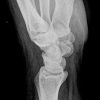

Handgelenk seitlich (radio-ulnar, 2. Ebene)

Indikation

Fraktur

Lagerung

sitzend - seitlich zum Tisch

Handgelenk, Unterarm und abgewinkelter Ellenbogen liegen streng seitlich auf. (Radius und Ulna deckungsgleich)

Zentralstrahl

senkrecht

Querzentrierung auf Gelenkspalt

Längszentrierung auf Objektmitte

Einblendung

distal einschließlich Fingergrundgelenke

Anmerkung

Ulnar und Radius müssen distal übereinander projiziert werden. Os Scaphoideum und Os Lunatum liegen übereinander, ebenso die Mittelhandknochen, bei Verdacht auf Subluxation des Os Lunatums, Zusatzaufnahme in Flextion und Reflextion der Hand notwendig (Stressaufnahme).

ggf. Tisch herunterfahren

Qualitätskriterien

Radius und Ulnar müssen deckungsgleich sein; Mittelhand, Handwurzelknochen und distaler Unterarm sollen abgebildet werden.